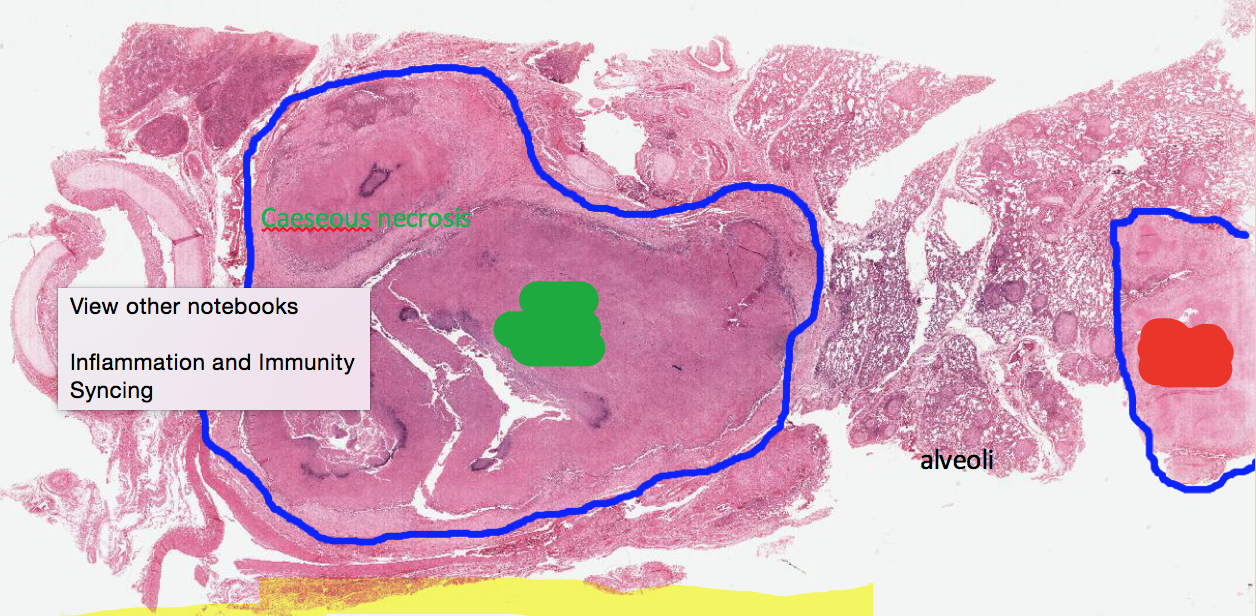

What is marked in green and red?

Green: Hilar Lymph Nodes

Red: Ghon Complex

Ghon’s complex is associated with what dz?

TB